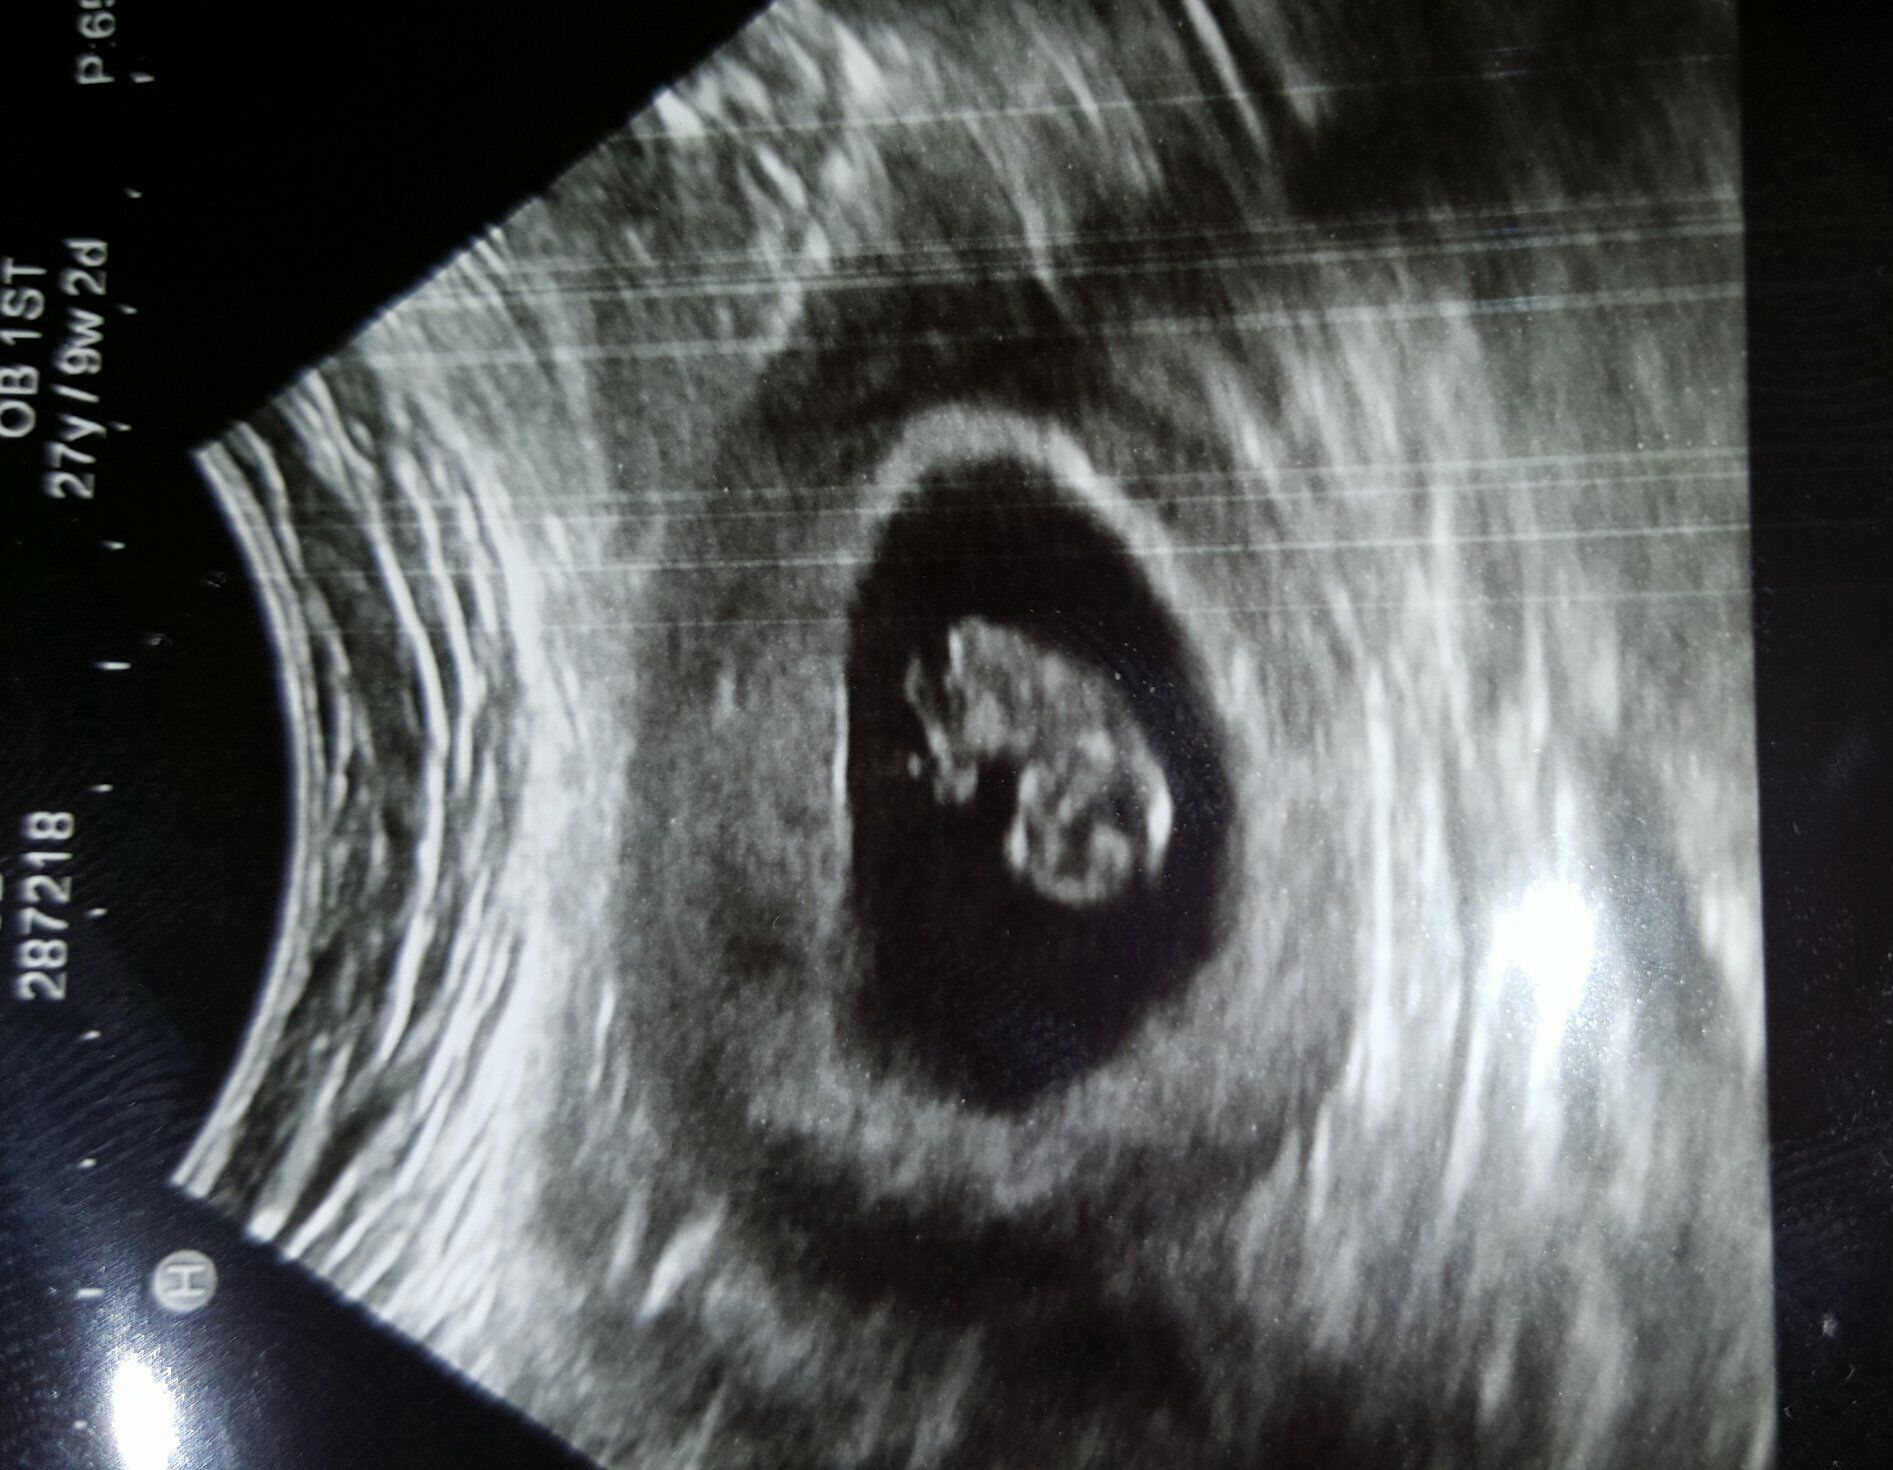

• This was at 7w1d, but baby was measuring at 6w5d. Next appointment is dec 11, and I will be 11 weeks. Hope we get another ultrasound then!!!!